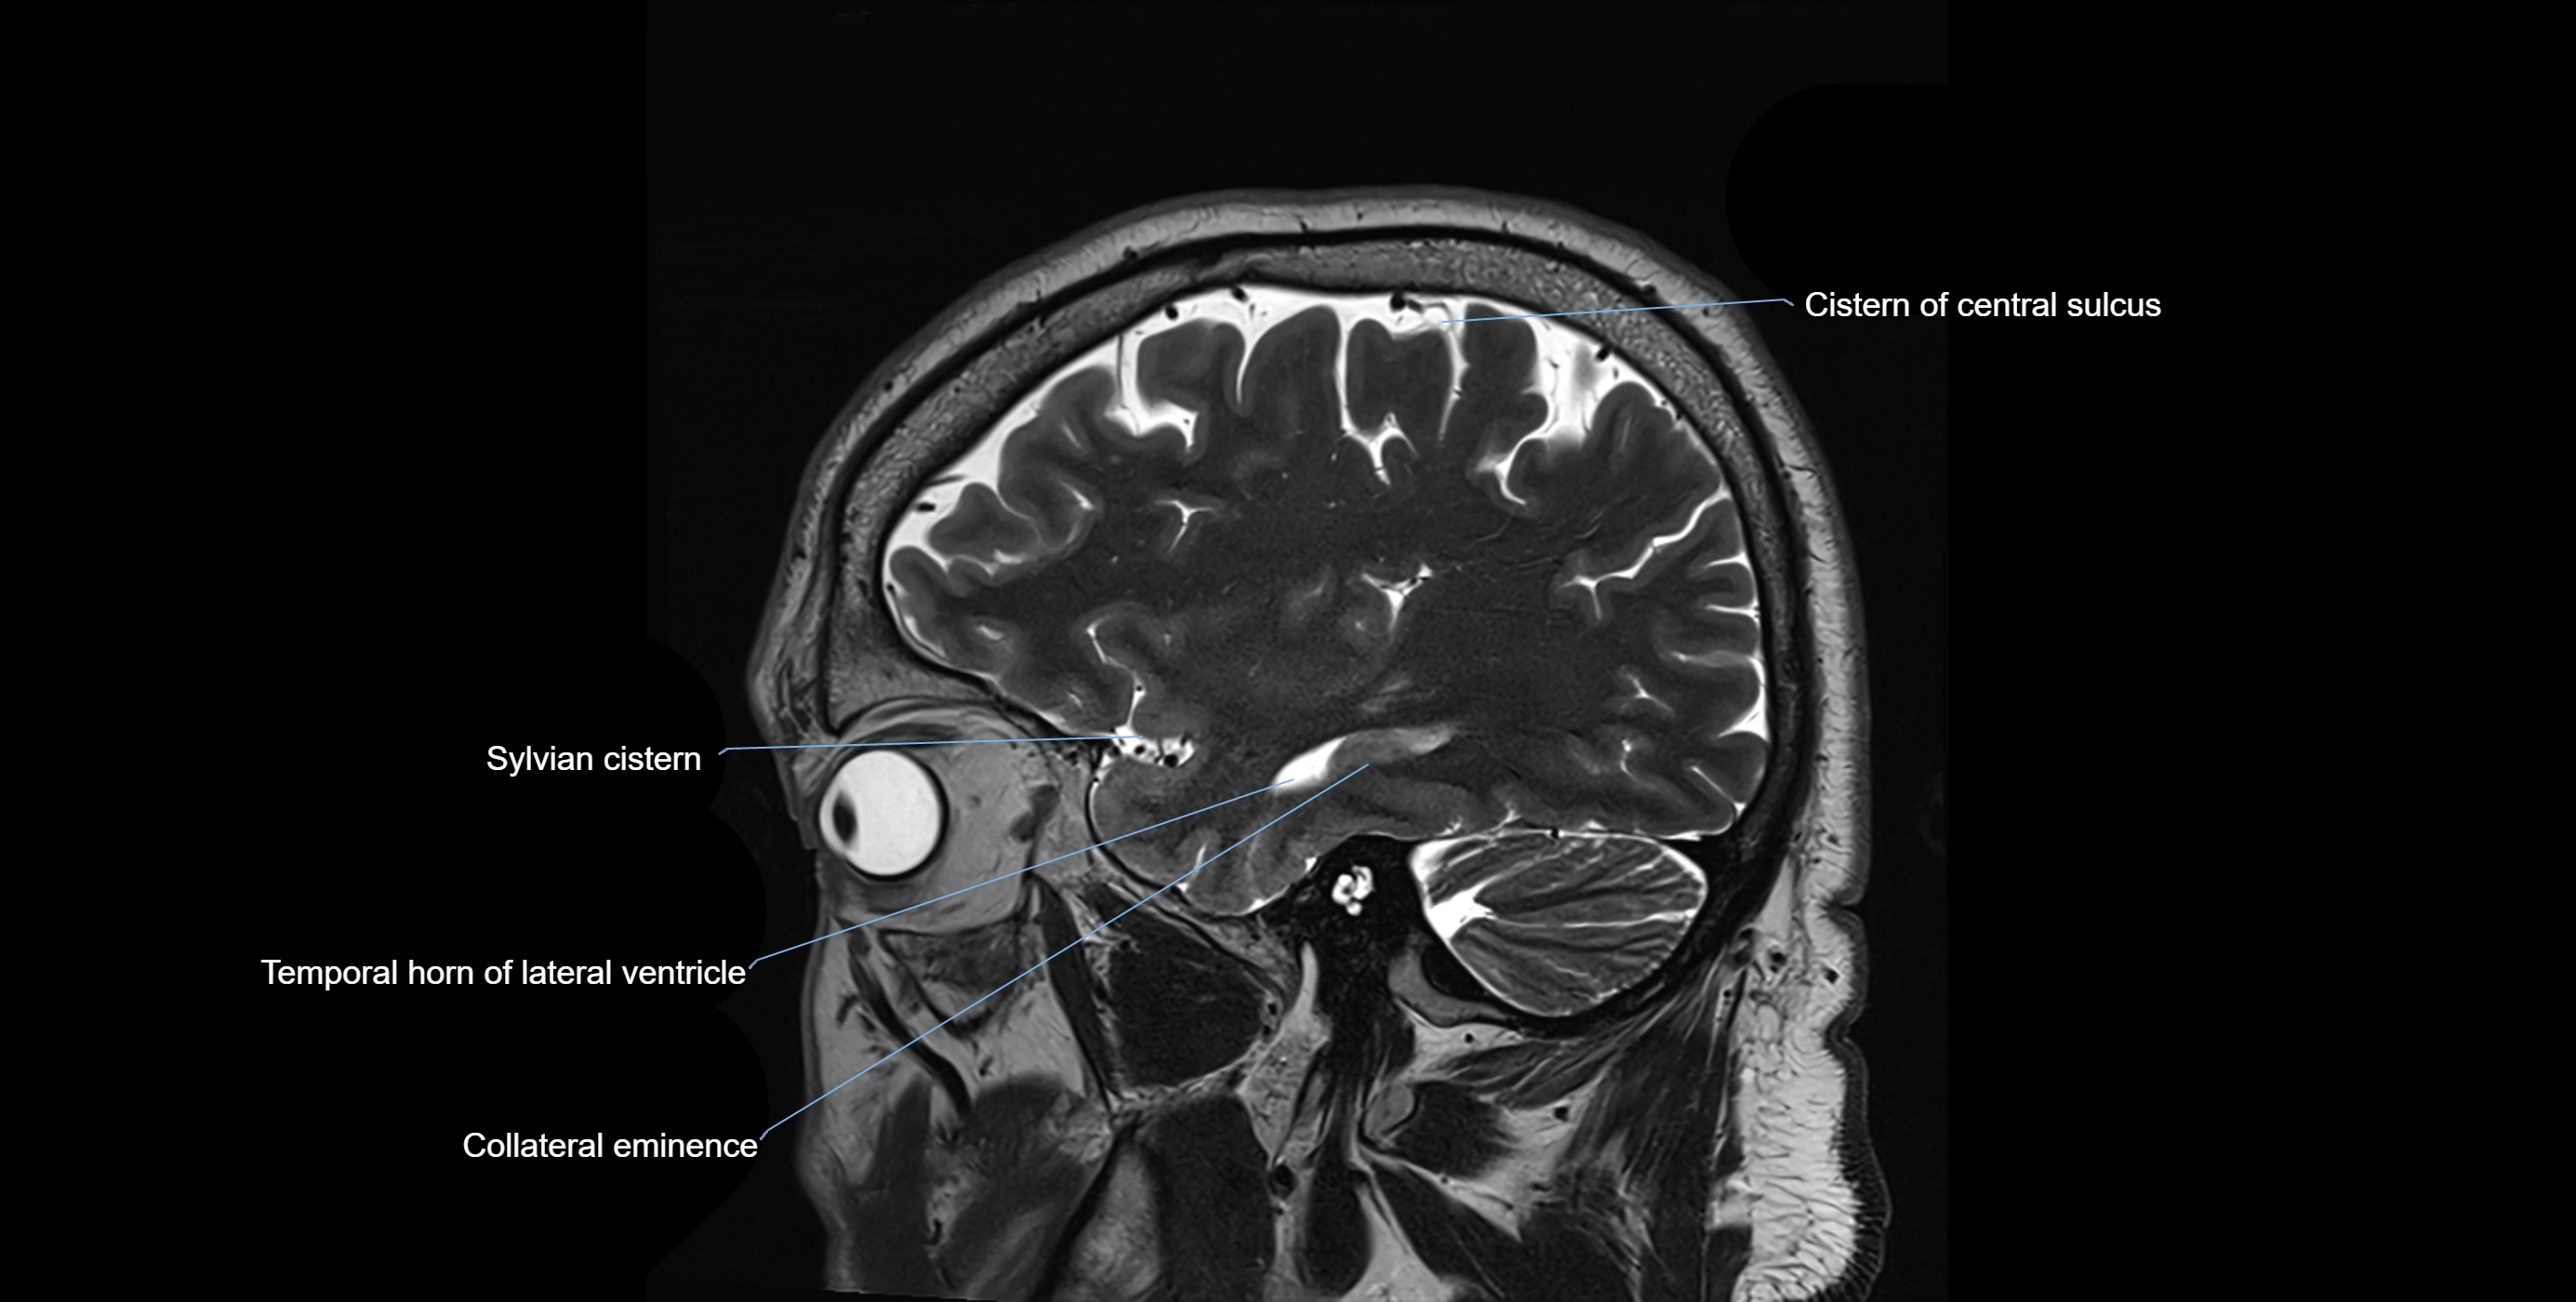

CT image

image